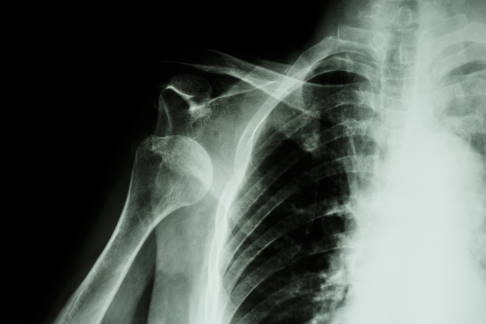

Bildgebung: Röntgen

Röntgenuntersuchungen zeigen zum Beispiel schmerzhafte Kalkeinlagerungen im Schultergelenk. © Gelenk-Klinik

Die Röntgenuntersuchung erlaubt die Untersuchung des Skeletts. Das Röntgen zeigt auch Kalkeinlagerungen ins Gewebe, eine häufige Ursache von Schulterschmerzen.

Auch die Dicke der Knorpelschicht lässt sich über die Messung des Gelenkspaltes zwar indirekt, aber genau bestimmen. So kann der Orthopäde eine Schulterarthrose feststellen. Auch arthrotische Veränderungen des Knochens durch Osteophyten (Knochensporne) zeigt das Röntgenbild.

Indem der Experte im Röntgenbild den Abstands des Oberarmkopfes zum Schulterdach misst, kann er Beschwerden auf ein Schulter-Impingement zurückführen.